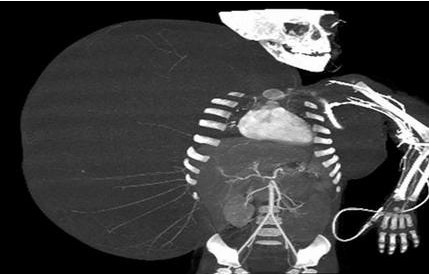

据美国《纽约每日新闻》5月29日报道,斯洛伐克男子Zoleik 10年来一直忍受着一种疾病的困扰,导致其脸部长有一个重达13磅(约12斤)的巨型肿瘤。而近日,经过手术治疗,他终于恢复正常的容貌。

据悉,Zoleik患有马德隆畸形症,该病导致其脸部的脂肪纤维疯长,从而形成一个巨型肿瘤。“它让我非常不舒服,转脖子都变得十分困难。”

Zoleik表示。 在长达10年的煎熬后,他终于可以通过手术治疗将肿瘤切除。手术过程长达5小时,但进行得十分顺利。手术后,Zoleik脸部的大部分肿瘤已被切除。